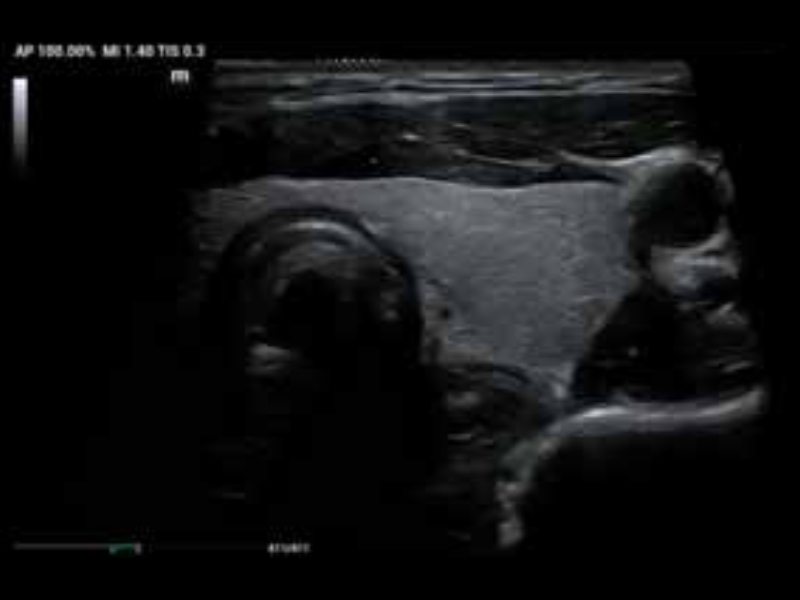

• zeus-fig5-1-3-uk

Tętniak aorty w trybie dopplera kolorowego